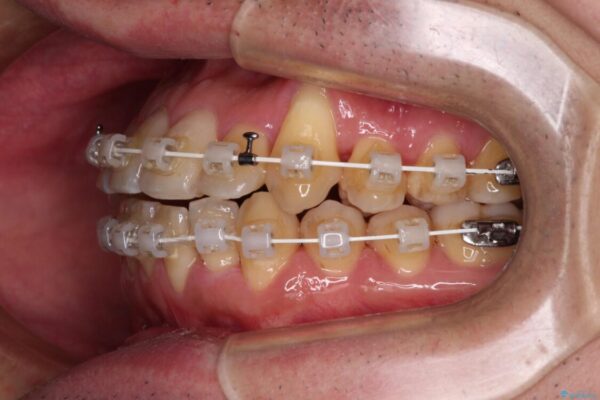

マウスピース矯正での自己管理には自信がないとのことで、ワイヤー装置による矯正治療を行うこととしました。

クロスバイトは、治療の過程で咬み合わせが大きく変化する期間があり、食事が取りにくくなってしまいます。

また、装置が対合歯と咬み合ってしまい、頻繁に脱落するなど、色々と面倒なことがあり、治療がスムーズに進まないことがあります。

デコボコが解消されると歯列が拡大される方向に動くため、出っ歯のような仕上がりとなることがあります。舌の突出癖を改善するトレーニングをしっかりと行っていただくことで、突出を抑制することができます。

治療途中

• 八重歯とクロスバイト 目立たないワイヤー装置で矯正治療 治療途中画像